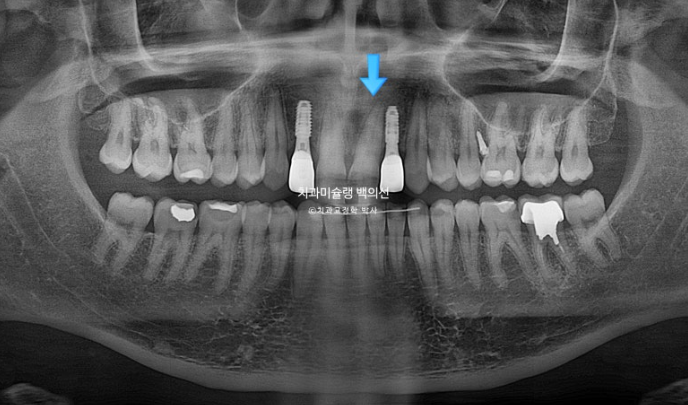

오늘은 부원장님 인비절라인 케이스를 보면서 앞니 2개가 선천적으로 없는 경우 (결손치) 인비절라인 교정 후 임플란트까지 치료 진행과정에 대해 보여드리겠습니다.

위 앞니 4개중 2개가 없습니다. 앞니가 크게 벌어져 있고 아래 앞니가 위로 솟아 위 입천장 잇몸을 칠 정도의 심한 과개교합이 있습니다.

앞니 자리로 밀려온 송곳니를 원위치로 보내어 결손된 앞니자리에 임플란트 2개를 하기로 했습니다.

치아 뿌리 평행도는 사랑니까지 좋습니다.